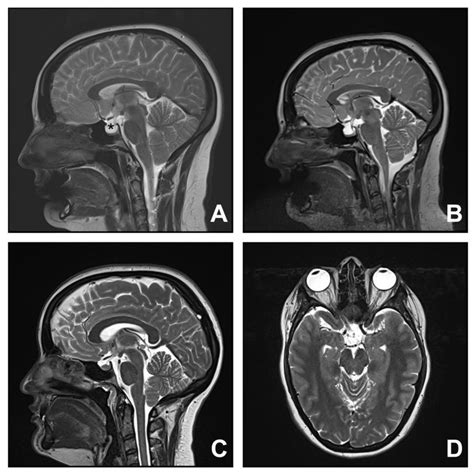

At its core, Cerebellar Tonsillar Ectopia describes the displacement of the cerebellar tonsils into the upper spinal canal. While often used interchangeably with Chiari malformation, it is important to note that the term "ectopia" typically refers to the physical descent of these structures. In many cases, this descent is identified incidentally during imaging studies like an MRI, performed for unrelated reasons such as persistent headaches or neck pain.

The primary concern with this condition is the crowding of the space at the base of the skull. Because the foramen magnum is a rigid, bony ring, any structure occupying space that should be reserved for fluid flow can lead to increased intracranial pressure. The degree of displacement is usually measured in millimeters, and while not every patient with this condition experiences debilitating symptoms, those who do often report complex neurological challenges.

To confirm the presence of Cerebellar Tonsillar Ectopia, physicians rely heavily on high-resolution imaging. The diagnostic process is essential for differentiating between simple ectopia and other structural pathologies. The following table summarizes the primary tools used in evaluation:

Magnetic Resonance Imaging (MRI) Gold standard for visualizing the brain and spinal cord structure.